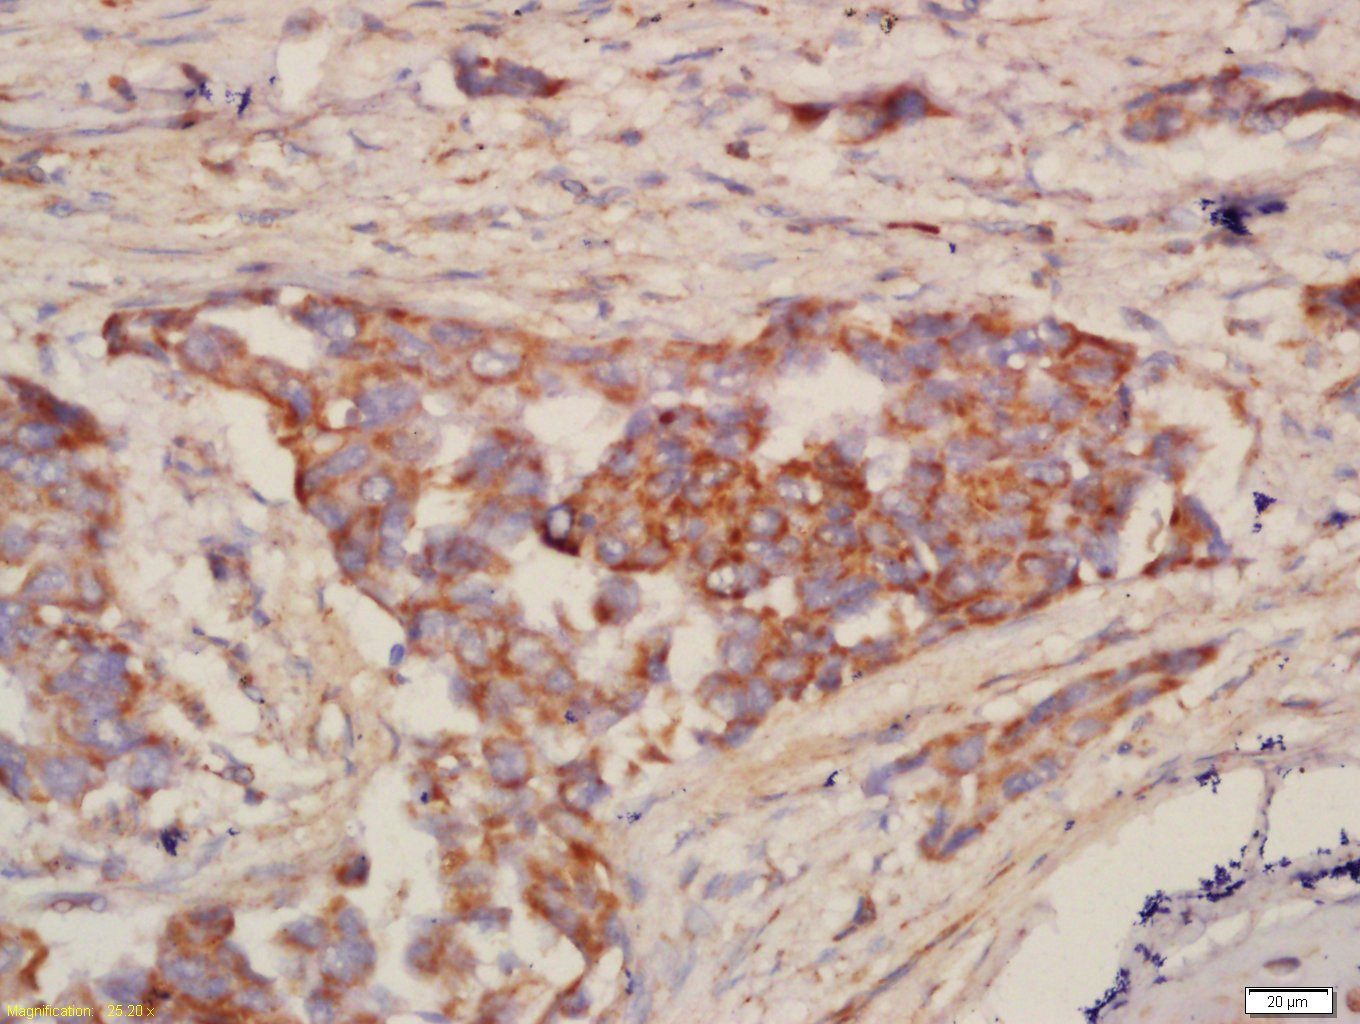

Tissue/cell: human lung carcinoma; 4% Paraformaldehyde-fixed and paraffin-embedded;

Antigen retrieval: citrate buffer ( 0.01M, pH 6.0 ), Boiling bathing for 15min; Block endogenous peroxidase by 3% Hydrogen peroxide for 30min; Blocking buffer (normal goat serum,C-0005) at 37℃ for 20 min;

Incubation: Anti-NALP12 Polyclonal Antibody, Unconjugated(bs-6864R) 1:200, overnight at 4°C, followed by conjugation to the secondary antibody(SP-0023) and DAB(C-0010) staining